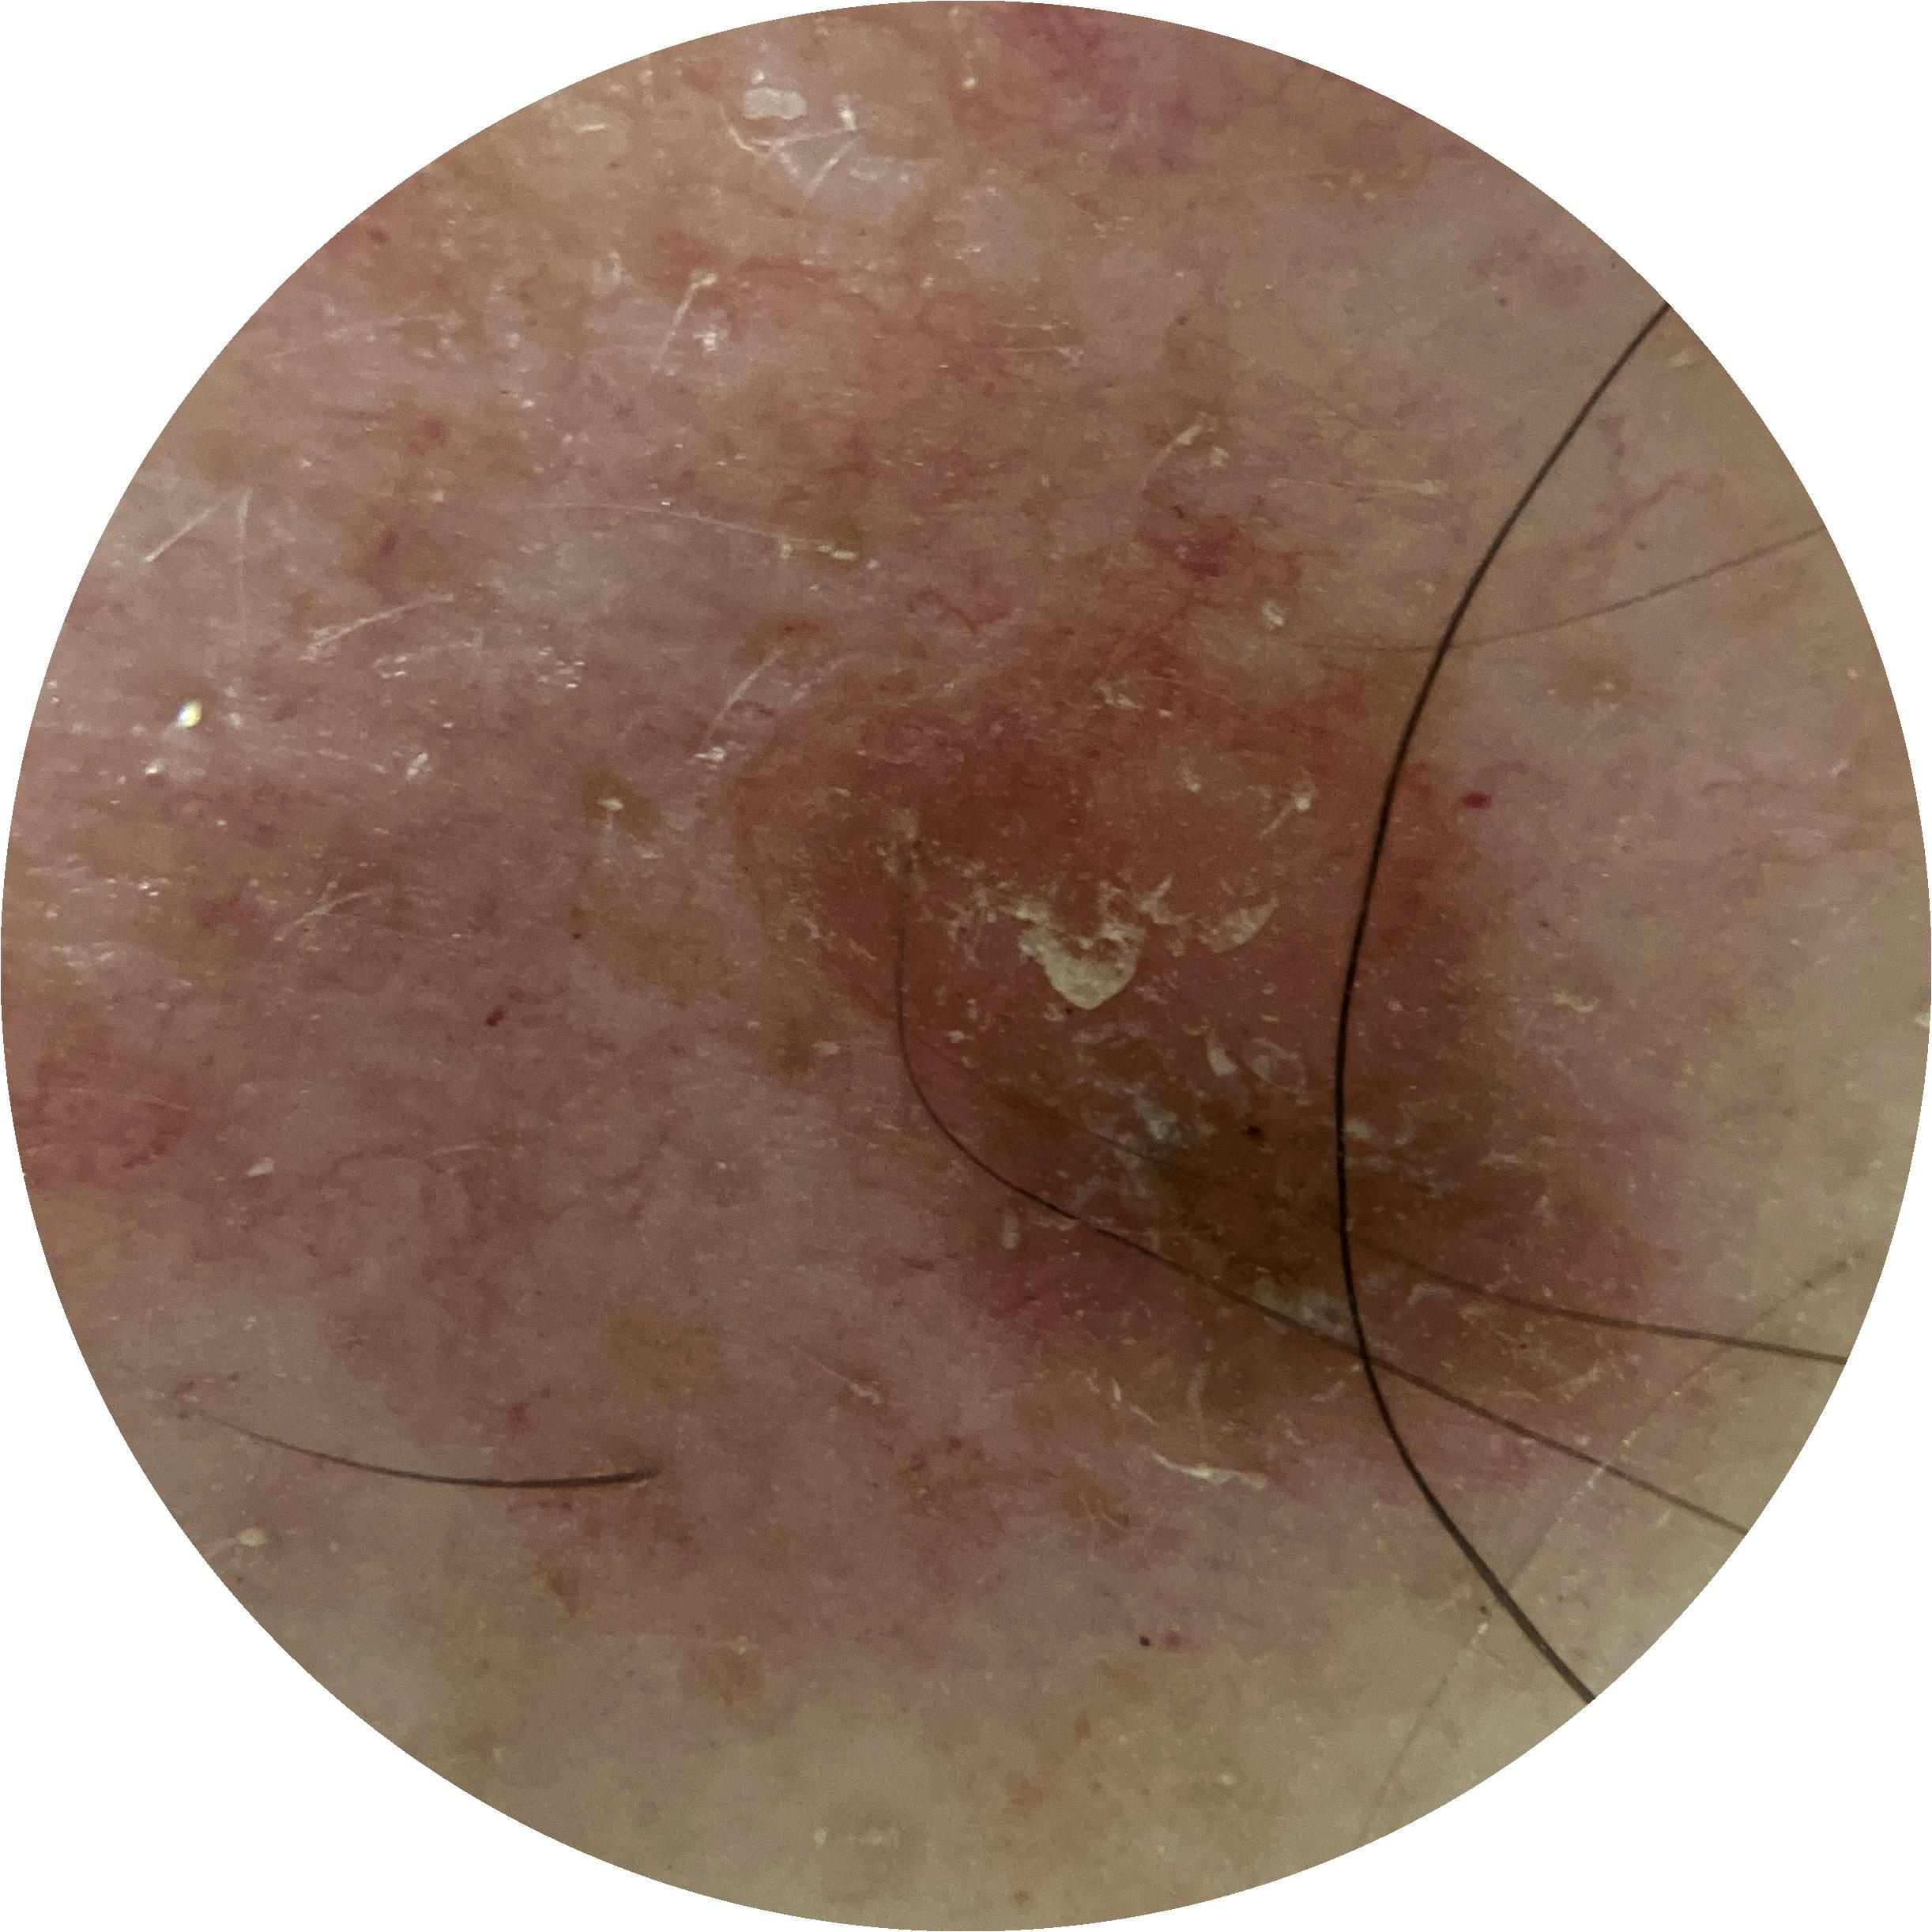

Field Value

acquisition_day 361

age_approx 60

anatom_site_1 Lower extremity

anatom_site_general lower extremity

concomitant_biopsy False

diagnosis_1 Benign

diagnosis_confirm_type single image expert consensus

family_hx_mm True

image_manipulation instrument only

image_type dermoscopic

lesion_id IL_4139461

patient_id IP_1989106

personal_hx_mm True

sex male